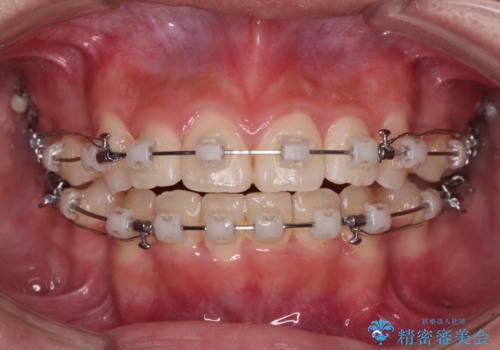

- 矯正装置

- クリアブラケット

- 2年9ヶ月

- 30回以上